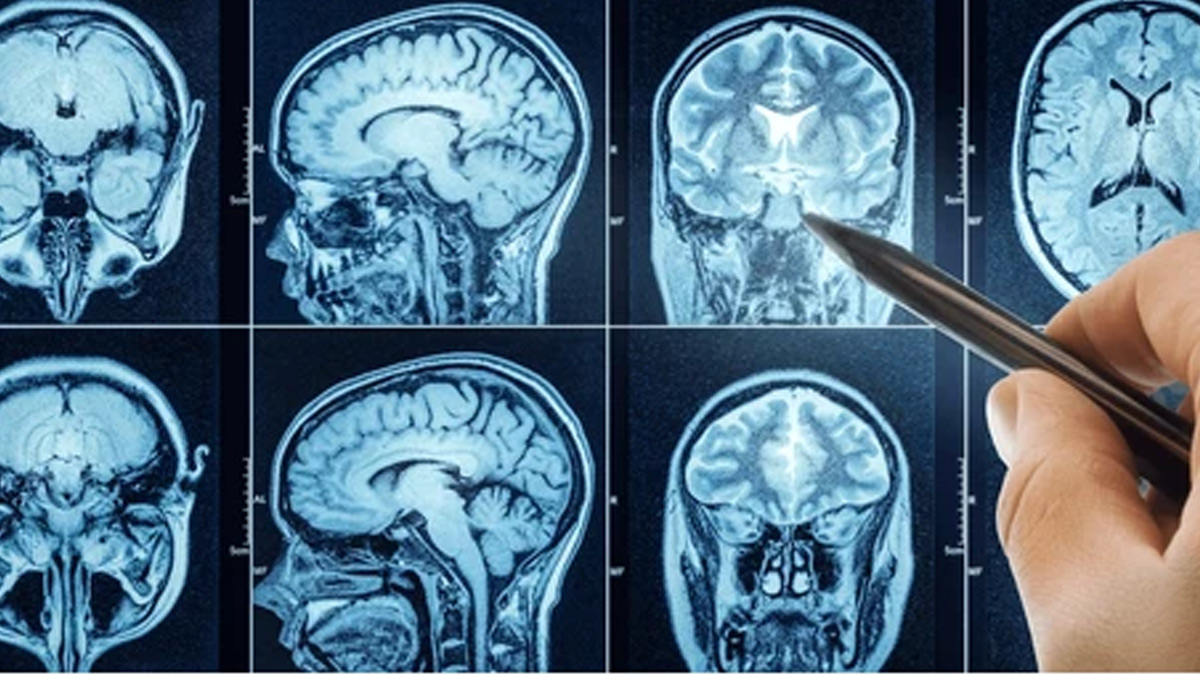

“DIPG begins in a section of the brain stem called the pons. Brain stems are located at the base of the brain and connected to the spinal cord. It is responsible for several important functions, such as heart rate, blood pressure, and breathing. It also controls the muscles and nerves responsible for walking, hearing, seeing, eating, and talking,” said Dr Souweidane.

DIPG is a form of glioma or a group of tumours that begins in the glial cells in the brain. These cells protect and support the nerve cells in the central nervous system, ensuring they work as they should, according to the National Cancer Institute.